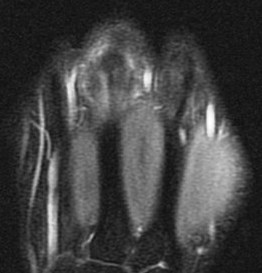

Figure 2 for case Boxers knuckle

Figure 2